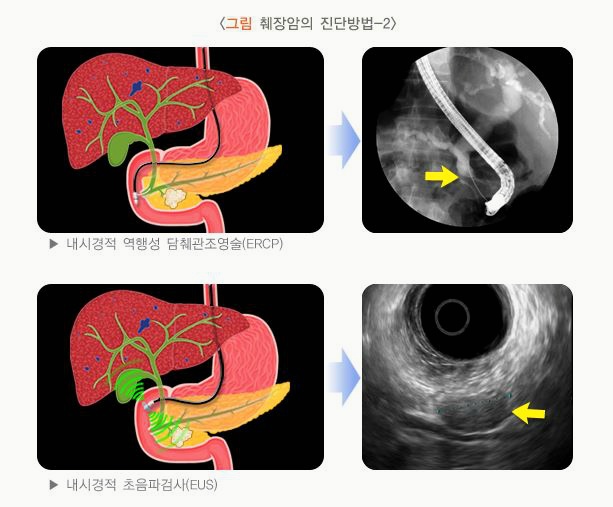

고로 이런 어정쩡한 통증이 있다라고 하면 빨리 검사를 받아보시는 편이 좋아요. 현재까지 췌장암 조기 증상에 관해서 말씀드렸는데요. 그럼 최장검사는 어떻게 할까요? 사실 최고 일전에 쉽게 해 볼 수 있는 검사가 복부 초음파 검사이예요. 초음파 검사는 배에 초음파 진단기를 문지르면서 보는 것이라서 간단하고 쉽게 가능한 검사입니다. 췌장을 잘 볼 수 있다고 한다면도 있다고하지만 췌장을 정확히 보기 힘든 경우도 있고요.

예컨대, 복부 비만이 있으시다면에는 초음파로 췌장의 전체 모양을 확인하기가 무척 어렵습니다. 뒤집어서 배에 살이 없으며 마른 경우에는 잘 보이예요. 또 위나 장에 가스가 많이 있는 처지에서도 초음파로 췌장을 확인이 완연하게 하기가 어렵습니다. 그리하여 사람에 따라서 가스 정황에 따라서 잘 보일 수도 있고 잘 안 보일 수도 있죠.

고로 췌장을 틀림없이 확인해야 할데 초음파로 잘 안 보이는 경우에는 대체안이 바로 복부 시티이라고 합니다. 씨티 를 찍어야 결국 췌장을 판연히 검증할 수 있 것이죠. 그리하여 증상이 있거나 또 초음파로 확인이 안 된다면 기필코 씨티를 확인하는 게 바람직해요. 오늘은 제가 췌장암의 조기 증상에 대해 말씀드렸고요. 검열하는 방법도 말씀드렸는데요. 우리 구독자님들 췌장검진 잘 받으시고요. 더 건강하시고 행복하시길 기원합니다. 고마워요.